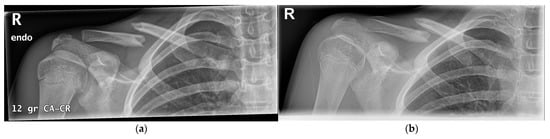

4.2.2. Operative Treatment